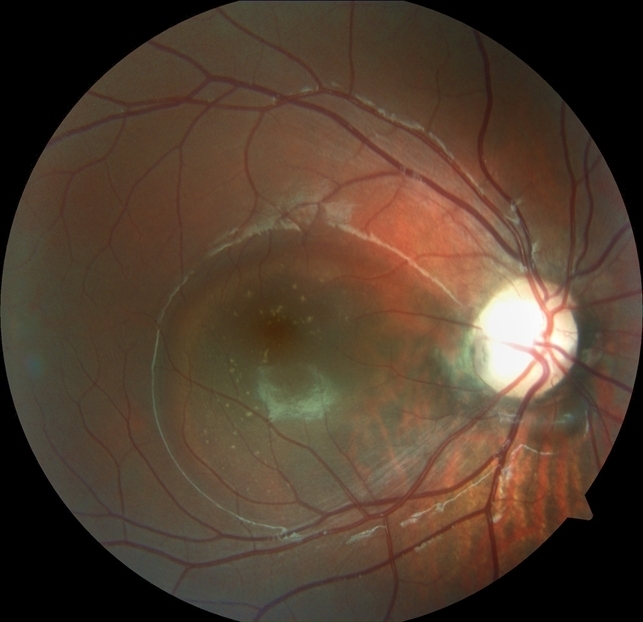

Приблизительно в 45-75 % глаз с врожденной ямкой диска зрительного нерва развивается серозная отслойка макулы. Ход развития макулярных осложнений:

- формируется ретиношизис внутренних слоев сетчатки, полость которого сообщается непосредственно с ямкой диска

- образуется разрыв наружных слоев сетчатки ниже границ полости ретиношизиса;

- отслойка наружных слоев развивается вокруг макулярного разрыва, что связано с притоком жидкости из полости ретиношизиса (отслойка наружных слоев сетчатки при офтальмоскопии может имитировать отслойку пигментного эпителия, но при ФАГ не отмечается характерной для последней гиперфлюоресценции);

Отслойка наружных слоев в конечном итоге увеличивается и облитерирует полость ретиношизиса. На этой стадии осложнение клинически неотличимо от первичной серозной макулярной отслойки.

Серозная отслойка сетчатки возникает преимущественно при ямке диска височной локализации. Эта отслойка имеет каплевидную форму и начинается от височного края диска, распространяясь на область макулы, иногда захватывает весь задний полюс, не выходя за пределы темпоральных сосудистых аркад.

- Со временем на задней поверхности отслоенной сетчатки могут откладываться сероватые преципитаты.

- При длительном существовании отслойки в ее зоне могут отмечаться альтерации пигментного эпителия,

- образование микрокист в толще отслоенного нейроэпителия,

- в редких случаях — сквозные макулярные разрывы.